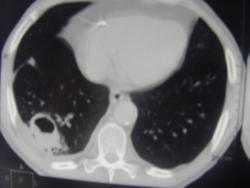

Больной лечился у невролога, провели проф ФГ- выявили деструктивную пневмонию, пролечилили, на Р контроле- ухудшение, клиники абсцесса не было, была боль в гр клетке спереди справа. Из анамнеза- лечился оперативно 6-7 лет назад по поводу рака верхней губы, в ООД не наблюдался последние годы. Данные за туб этиологию сомнительны, как мне кажется, очагов отсева по слоям не вижу,  хотя мож не так смотрю. Ваше мнение коллеги, абсцесс это или нет?

Его направят к торальному хирургу в область, хирурги у нас редко что пунктируют, да здесь клиники никакой не было абсцесса, а сейчас больной и вовсе отлично чувствует, это после 3недельной а/б терапии, только что на третьем  Р контроле- ухудшение. Напишу абсцесс тогда.

По опыту хочу сказать, что в настоящее время классической клиники абсцесса можете и не увидеть. Очень она изменилась. В данном случае контроль  должен помочь. В связи с тем, что стенки имеют разную толщину и вокруг почти нет изменений, больше склоняюсь к полостной форме рака.

Спасибо, на послойных просмотрах тоже не увидела никаких отсевов. Хотя туб и онко отсевы ничем не отличались бы, да? Но СКТ должно и их отдифференцировать, чтобы больного направить на лечение по профилю.